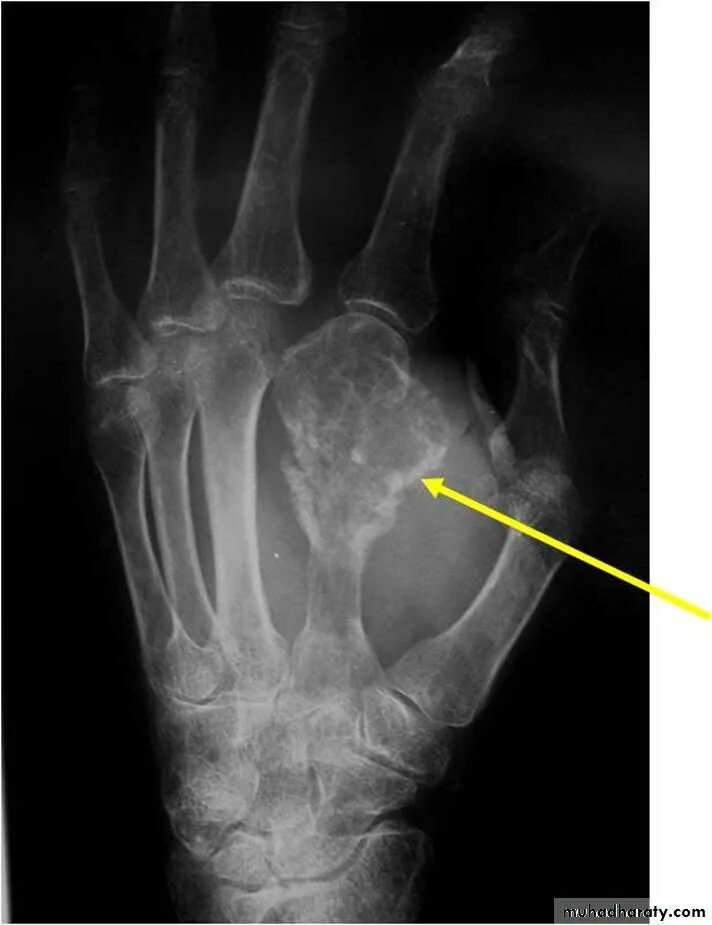

Перелом кисти руки что делать